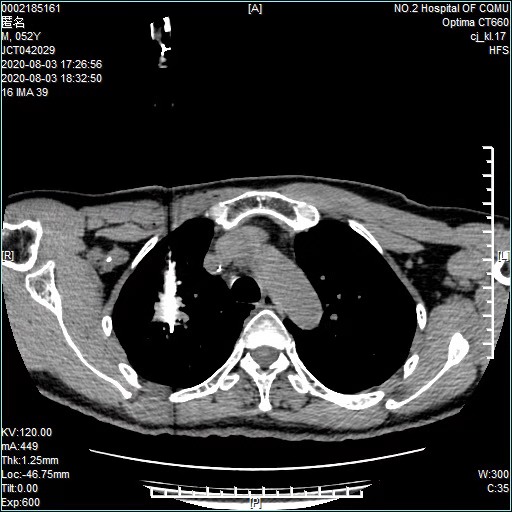

经过充分的术前准备、评估,2020年8月初,郑先生接受了射频消融微创治疗。术中,江德鹏教授在患者体表定位后,将单极射频肿瘤消融电极针,准确置入病灶中心部位,然后开始射频消融治疗。在治疗过程中,又适时调整穿刺方向及深度,密切观察患者的反应及生命体征。

(术中)

整个手术耗时1小时左右,因不必全身麻醉,患者术中未诉任何疼痛。消融完毕行胸部CT扫描,达到了完全消融的影像学特征,未见明显气胸和出血等情况。神奇的是,术后第二天,郑先生的一些胸部不适症状就消失了,目前,郑先生在医生的指导下规范治疗,疾病没有进展。